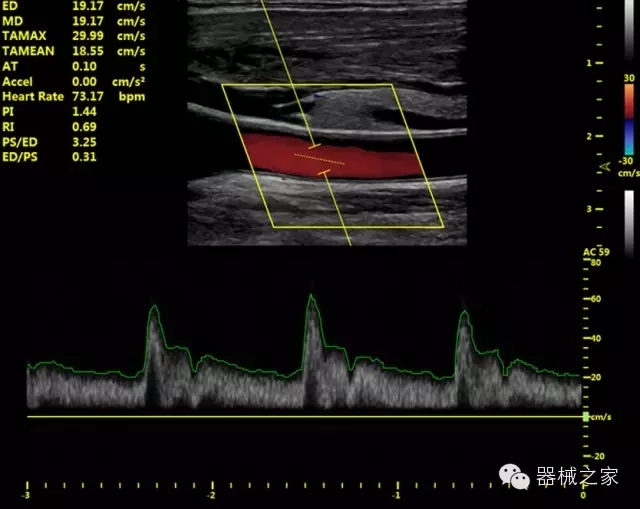

臨床圖片賞析

·IMT血管內(nèi)中膜自動(dòng)測(cè)量:為血管性疾病評(píng)估提供了有效的評(píng)估手段;